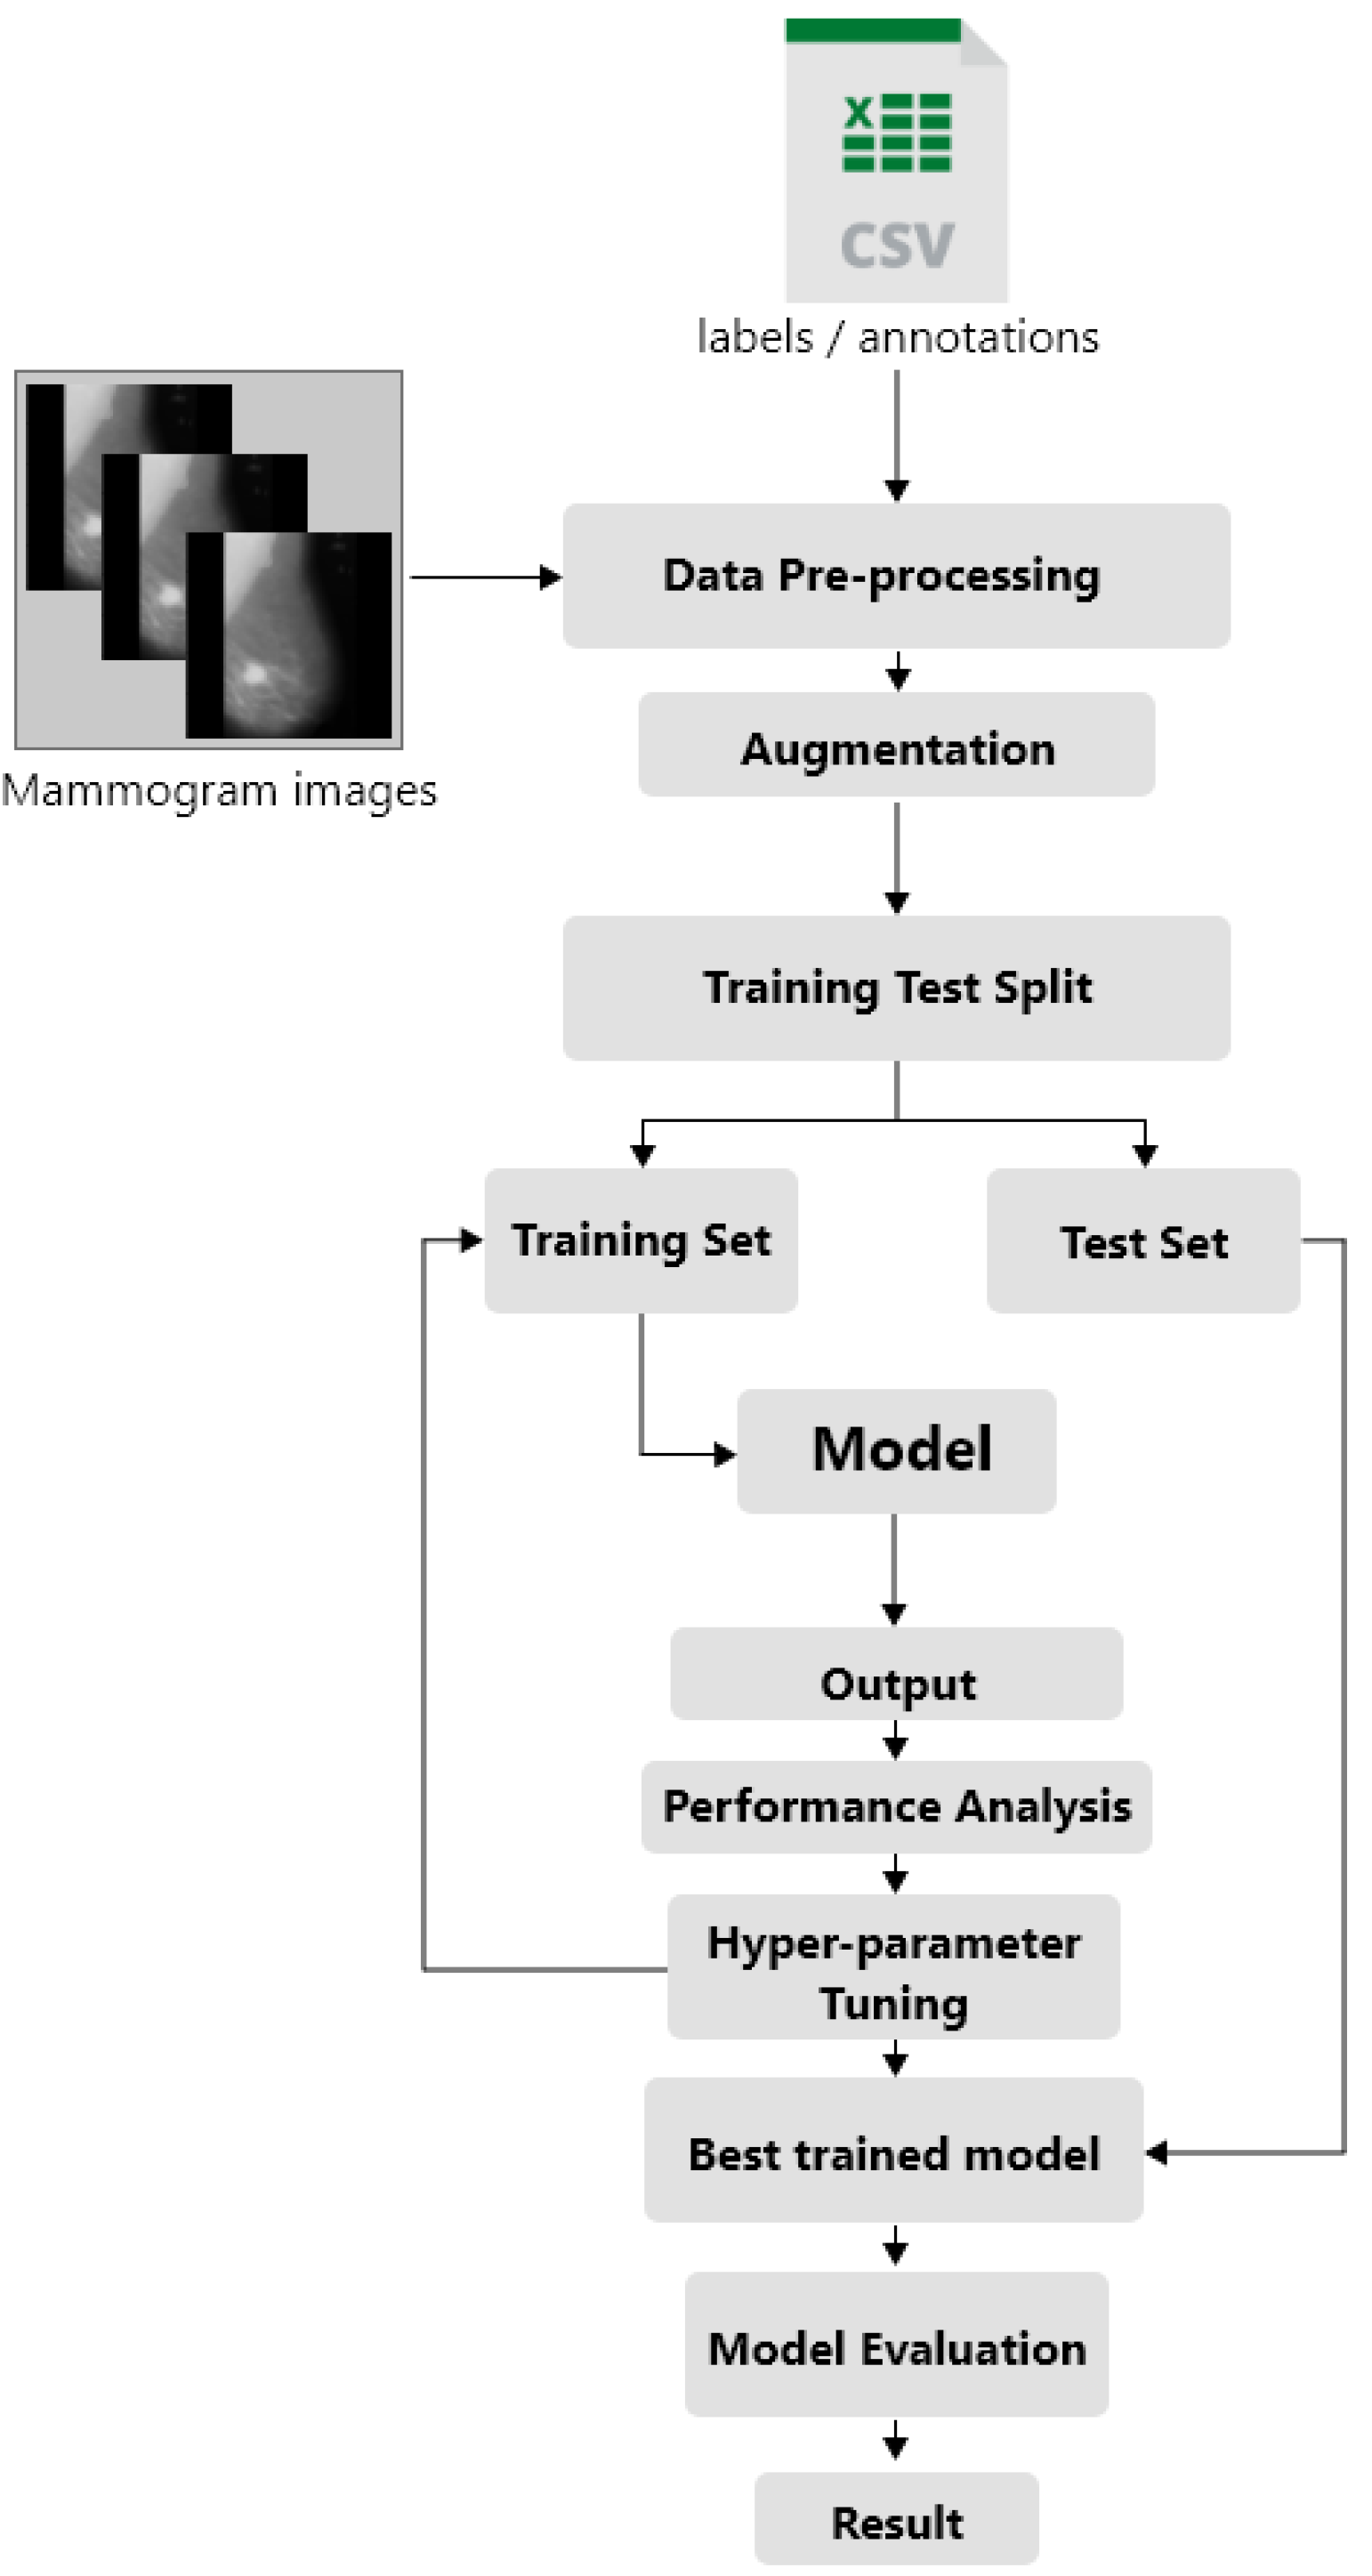

3.1. Dataset and Preprocessing